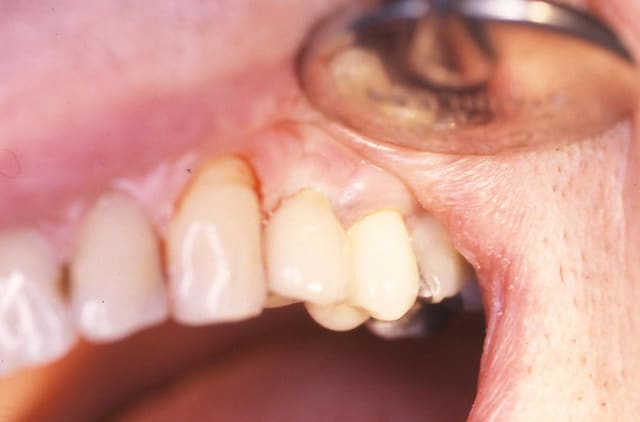

Patiente présente une perte alvéolaire de la table externe suite à fracture radiculaire.

J'ai réalisé un lambeau tracté coronairement mais je pense que certains auraient peut-être réalisé un lambeau conjonctif palatin.